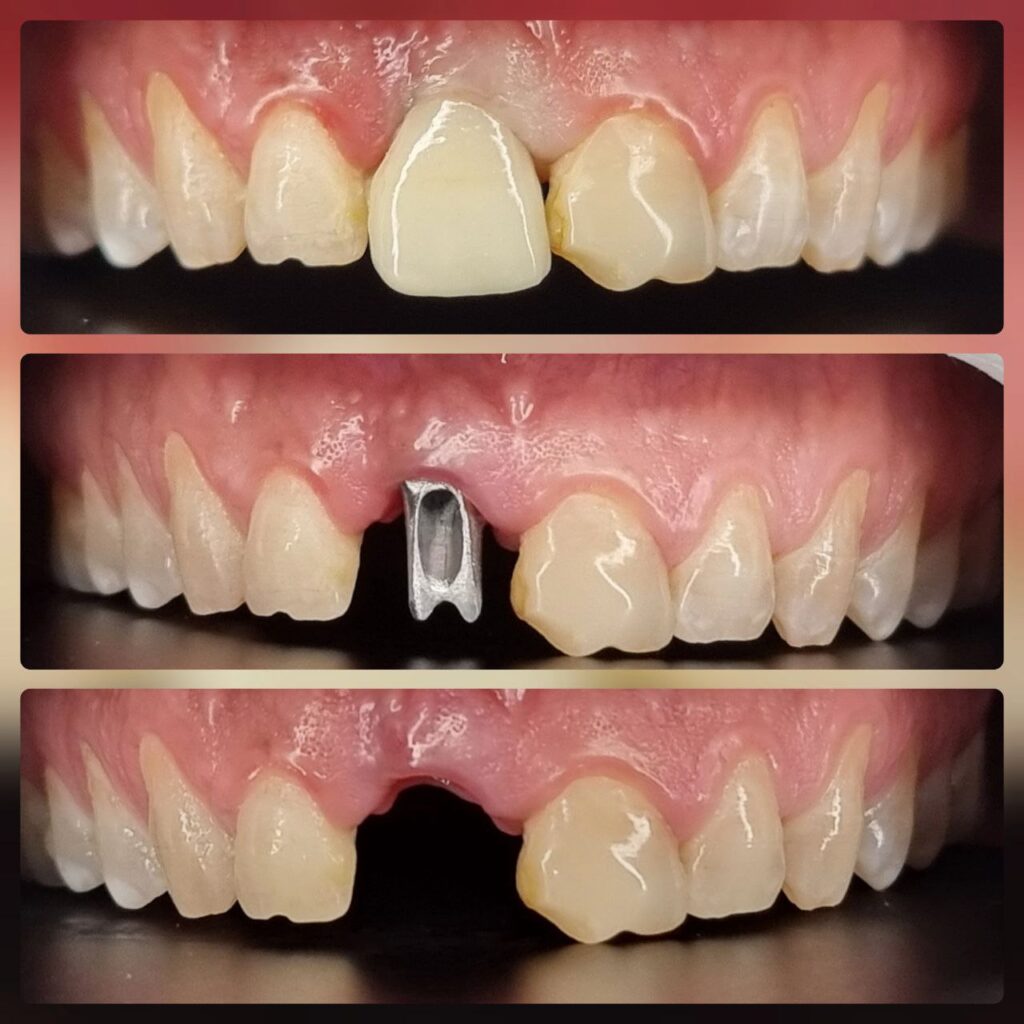

کاشت ایمپلنت دندان

اطمینان حاصل کردن از اینکه دندانهایتان به نحوی زیبا و طبیعی جایگزین شدهاند، از اهمیت بسیاری برخوردار است. ایمپلنت دندان به عنوان یک روش درمانی دائمی در دندانپزشکی شناخته میشود که حاصل آن، یک دندان زیبا و طبیعی در دهان شما خواهد بود.

هرچند که این روش درمانی هزینهی بیشتری نسبت به روشهای دیگر دارد، اما ارزش زیبایی که ایجاد میکند، قابل انکار نیست. ایمپلنتها به قدری شبیه به دندانهای طبیعی هستند که به سختی میتوان آنها را از دیگر دندانها تشخیص داد.